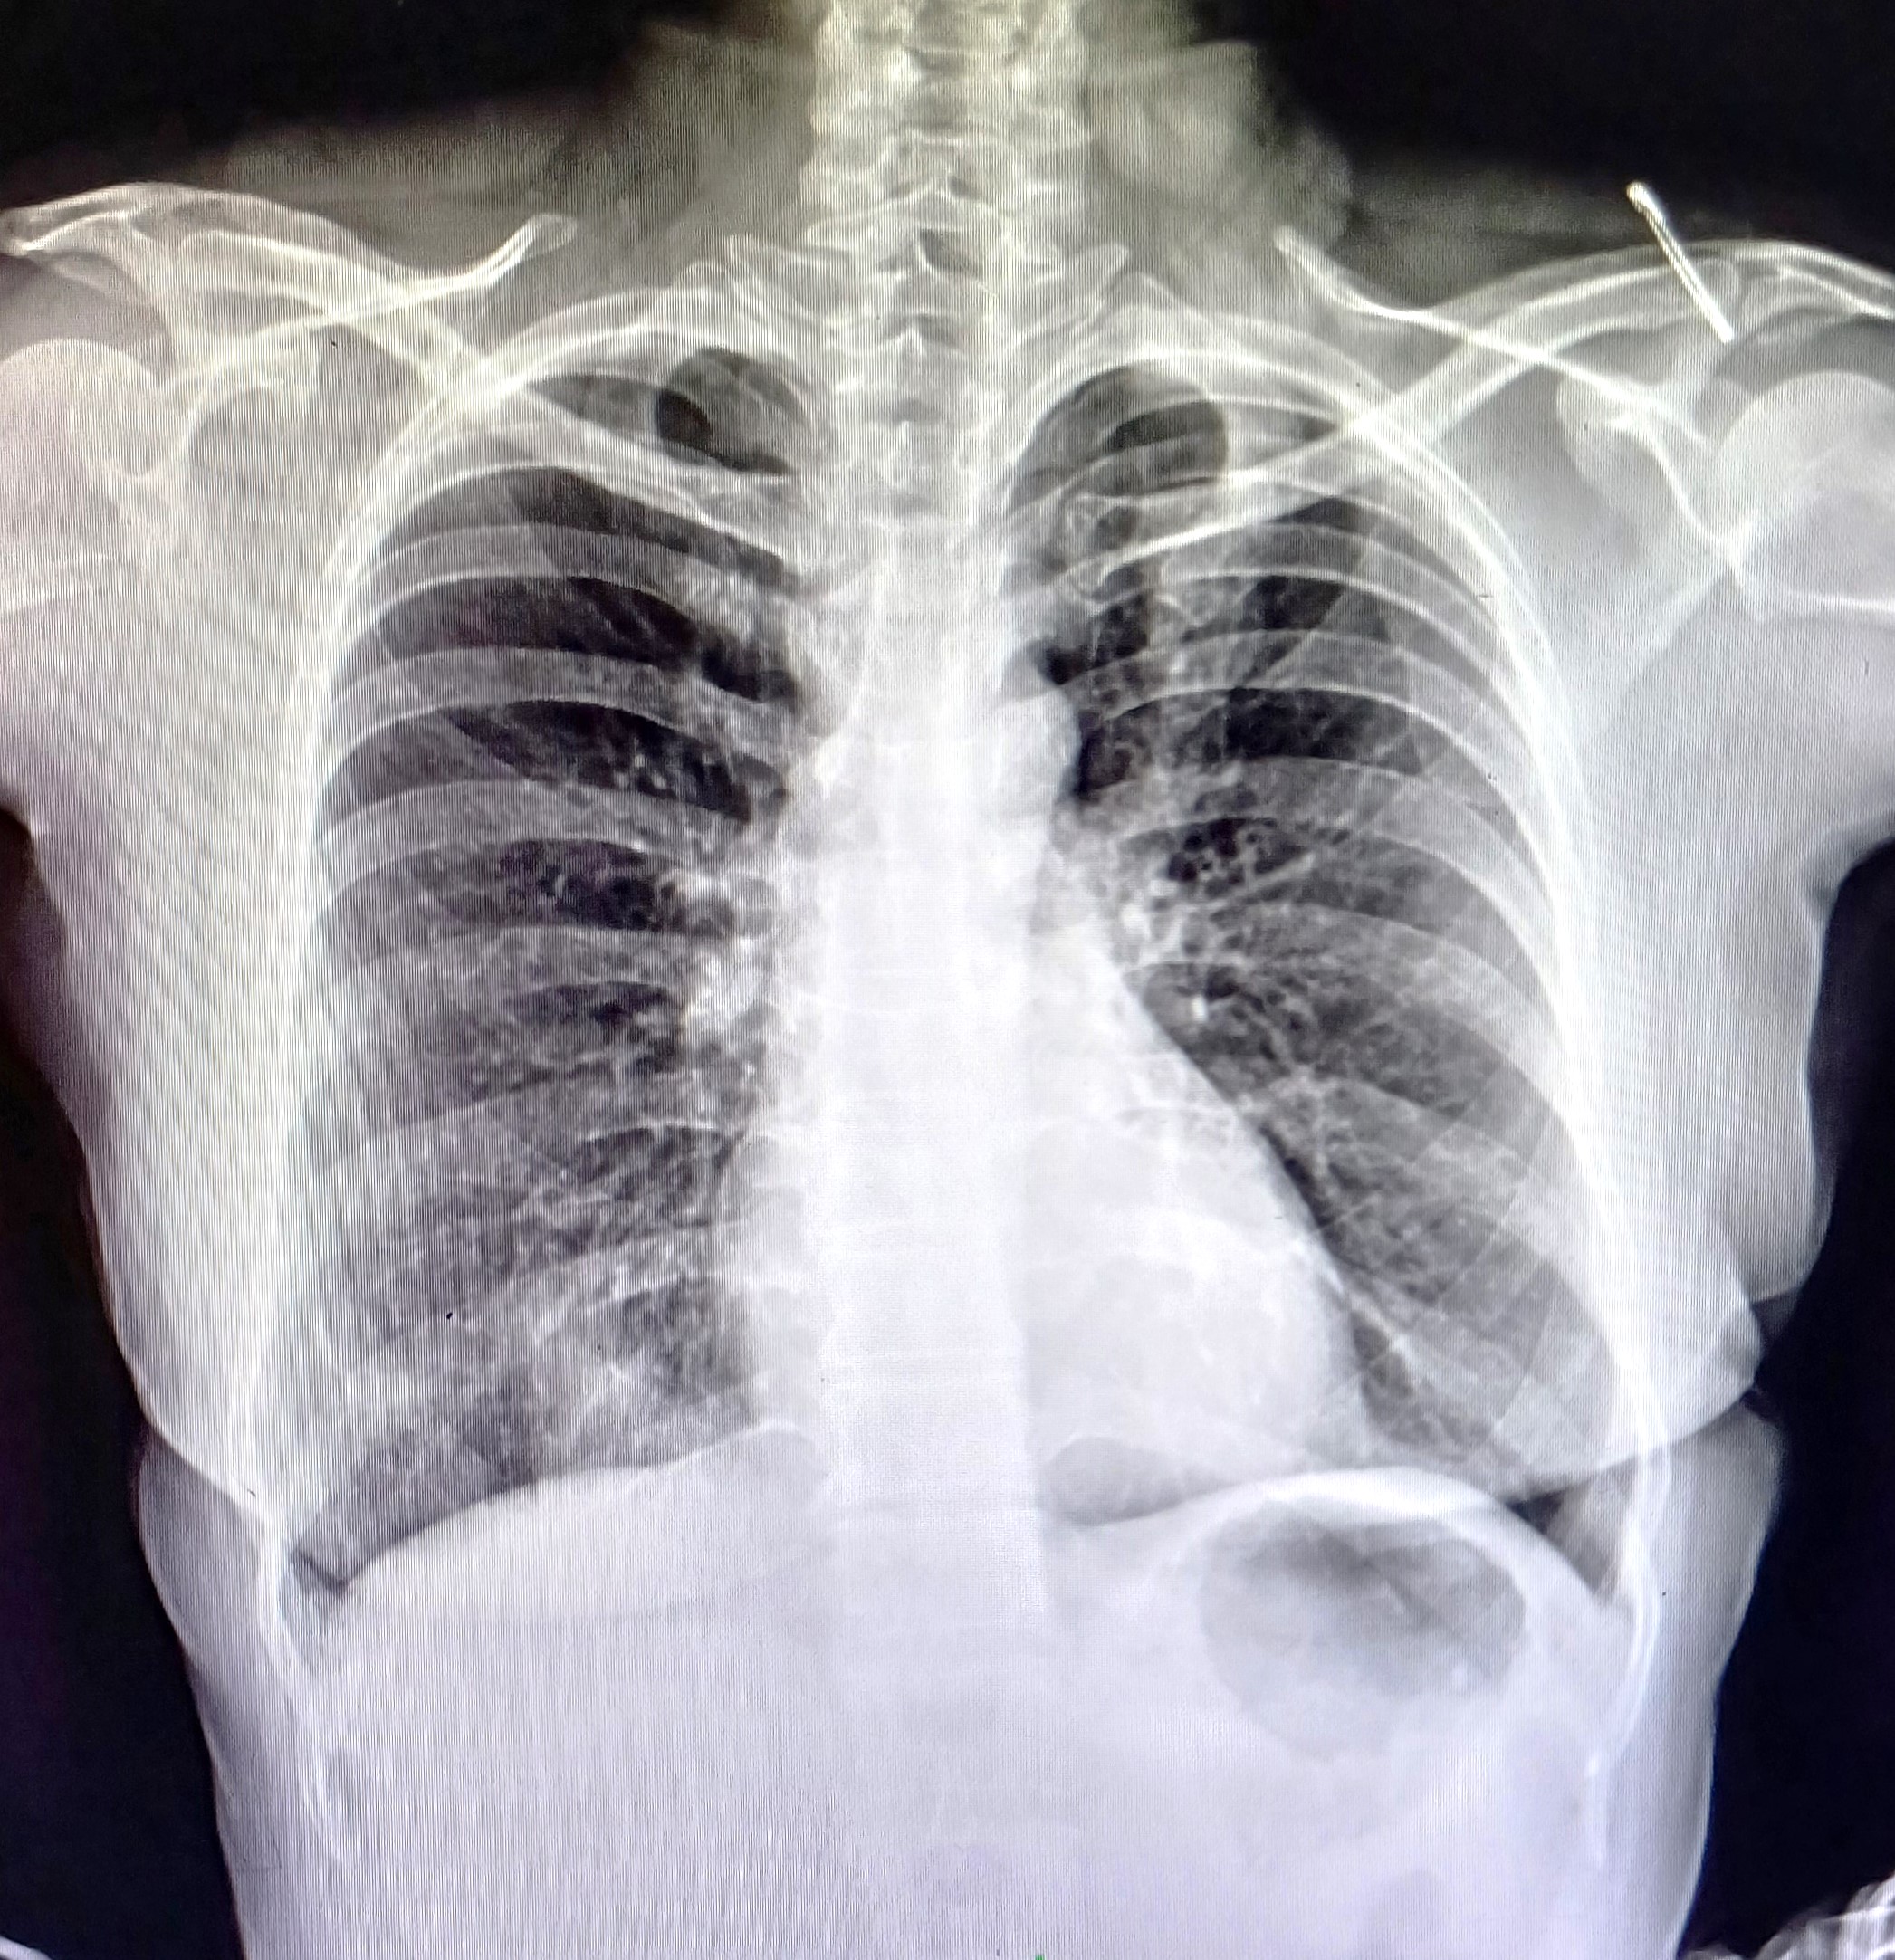

| 4 | IGGMC, Nagpur, Nagpur | P2 | 29-4468 | Moh. Salehuddin | Consent taken on Paper | 68 Yrs. |

Provisional Diag : Miliary TB?

Final Diag : Miliary TB |

TB Case (Confirmed) | Bilateral Infiltrate Query Miliary | Abnormality visible on x-ray |